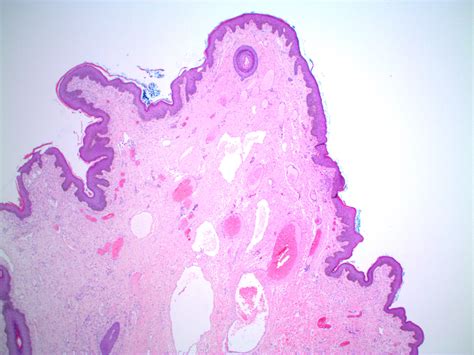

A skin tag is a small, soft, pedunculated growth that sticks out from the surrounding skin. These growths are typically composed of a loose network of collagen fibers and blood vessels, covered by a thin layer of epidermis. While they can appear anywhere on the body, they tend to develop in areas where skin rubs against skin or clothing, which is why a skin tag on nipple or the surrounding areola is not uncommon.